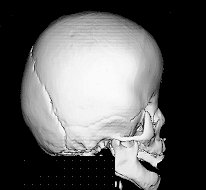

Synostosis is the premature closure of one or more of the calvarial sutures.  Such fusion limits the abilty of the skull to expand in a direction perpendicular to the suture, resulting in characteristic head shapes.  The sutures are dynamic: as the brain grows, the sutures expand, adding new bone.  The brain normally doubles in size during the first 6 months, and again by 2 years of age.  Hence, in hydrocephalic children, the head may be unusually large.  If the sutures are compressed, either mechanically or due to failure of underlying CNS expansion, the sutures may either resorb or fuse.  Synostoses are either primary (fusion of single suture as an isolated event) or secondary (for instance, in association with several syndromes discussed below, often involving more than one suture).  The prevalence of primary synostosis is about 1/4000 to 1/1000 live births.  Diagnosis is made on the basis of characteristic head shape, presence of ridges overlying fused sutures, rotation of facial landmarks.  A reconstructed 3D CAT scan makes the defect immediately apparent.  Clinically, signs of increased intracranial pressure (ICP) may also be present (vomiting, lethargy).  Some synostoses are diagnosed in the context of syndromes.

Sagittal

• most common, 58% of all synostoses

• 2-3 x more males than females

• dolichocephalic/scaphycephaly (long-headed/keel-headed)

• May be turricephalic (tower-headed)

• frontal and/or occipital bossing may be present

• frequently, early closure of anterior fontanelle

• about 10% associated with increased ICP

• shape complicates vaginal delivery